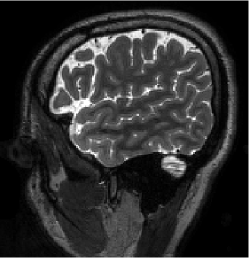

IV-B Data for training and testing the algorithm

The MRI data used for this study were acquired using a 3D T2 CUBE sequence with Cartesian readouts using a -channel head coil. The matrix dimensions were 256 232 208 with mm isotropic resolution. Fully sampled multi-channel brain images of five volunteers were collected out of which data from four subjects were used for training, while the data from the fifth subject were used for testing. Since the readout is fully sampled, we evaluated the inverse Fourier transform of each readout. We retrospectively undersampled the phase encodes to train and test the framework; we note that this approach is completely consistent with a future prospective acquisition, where a subset of phase encodes can be pre-selected and acquired. All the experiments were performed with variable-density Cartesian random sampling mask with different undersampling factors mentioned at their use.

Out of the total slices for each subject, we selected slices that had images of parts of the anatomy for training. The coil sensitivity maps were estimated from the central k-space regions of each slice using ESPIRiT [42] and were assumed to be known during experiments. Thus, the training data had dimensions in as and testing data had dimensions . The testing was performed on slices out of available for the test subject since the initial and the last slices did not have any brain region but noise. To reduce the sensitivity to acquisition settings, including undersampling patterns, we used different variable density Cartesian pseudo-random sampling masks for each training slice. The same sampling mask was used for the data from all coils of the same slice. The undersampling factors are mentioned at their use in the experiments. The sampling masks used during the testing were different from the ones used during the training.